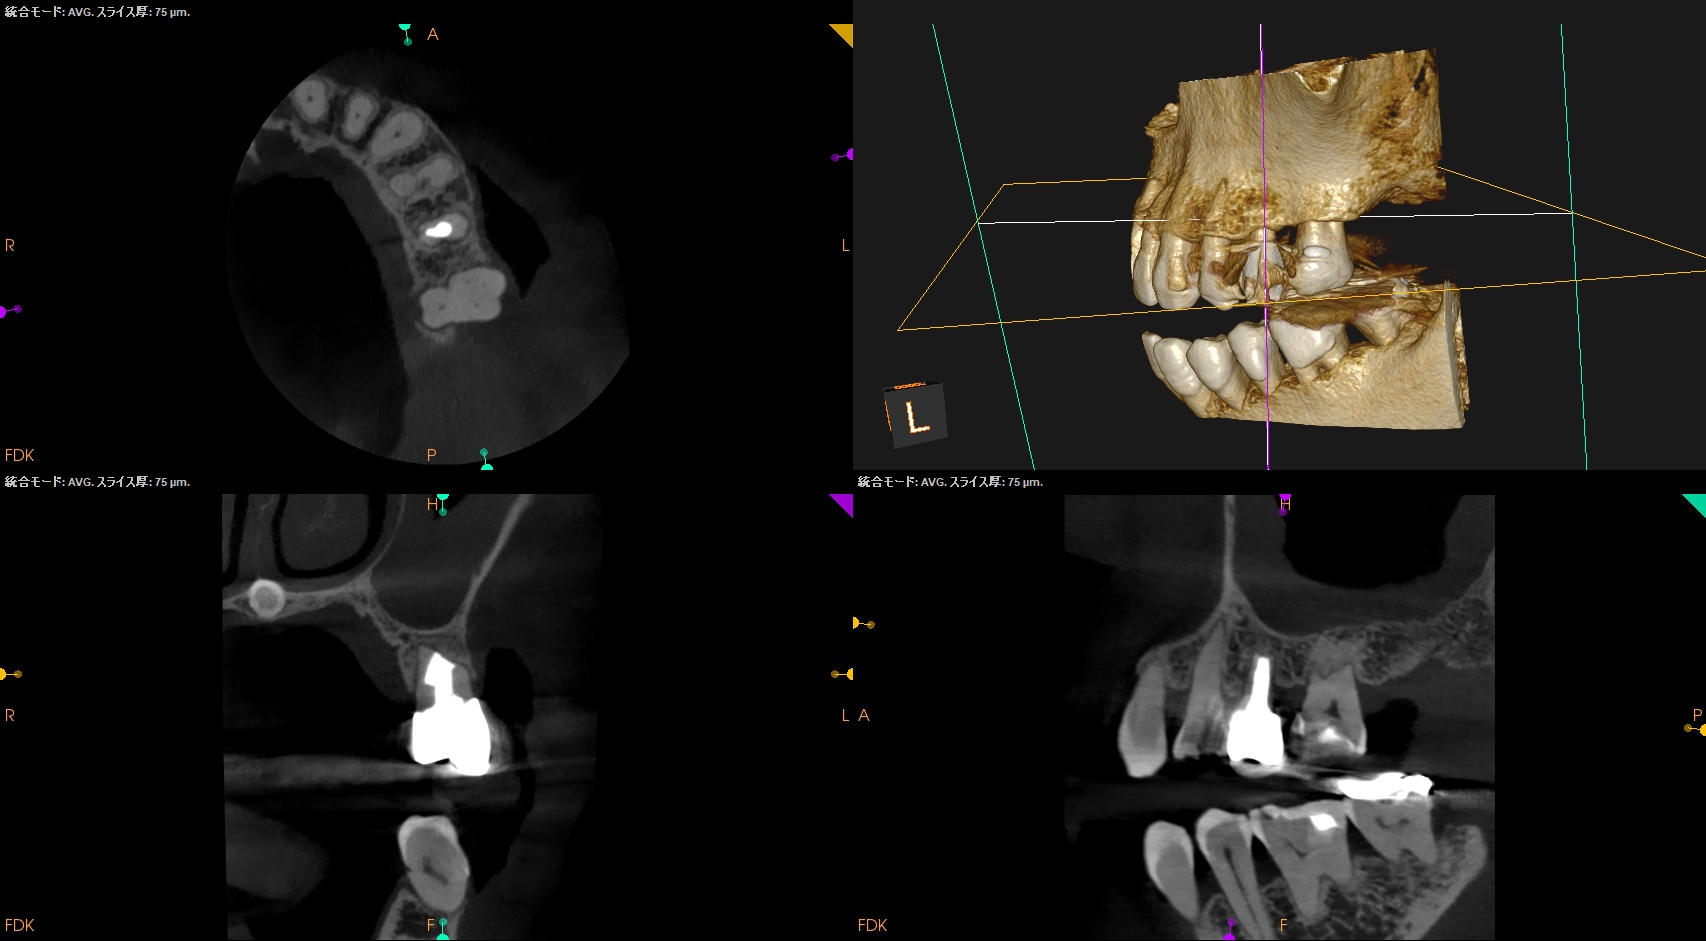

#13 Apicoectomy 1yr recall(2026.3.25)

1年前と比較してみた。

根尖病変は消失し、外科治療に関わる骨欠損も完治した。この状態ならセラミックに変えてもいいだろうが、術前の状態では無理である。

歯内療法は歯槽骨の再生が図れる唯一の歯科医療である。

これぞ再生療法だ。